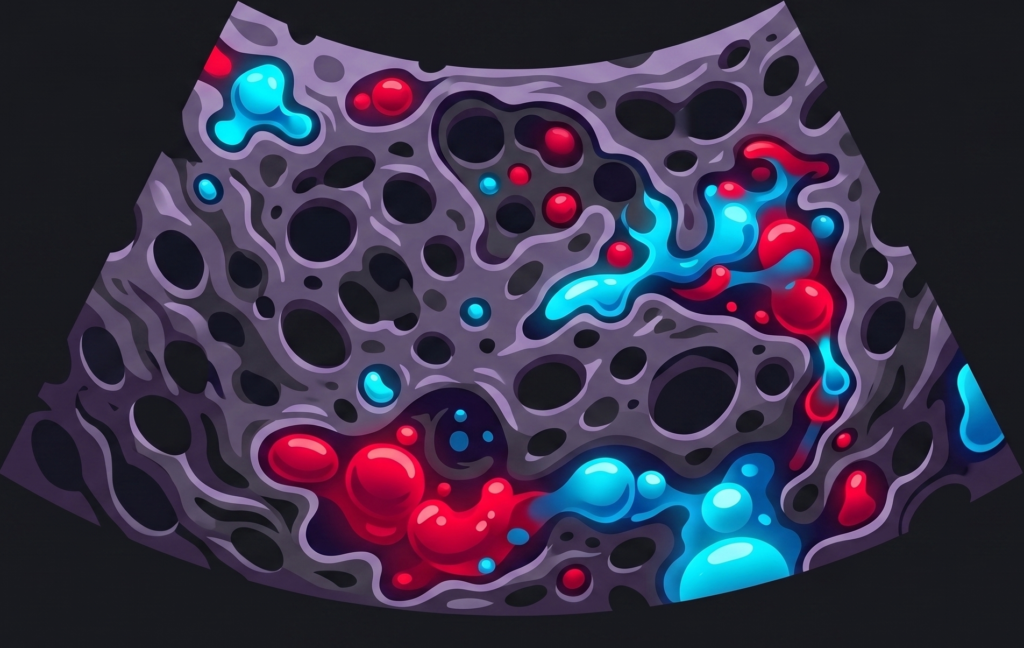

Placenta Accreta Spectrum: Pearls & Pitfalls

While US is the primary screening tool, MRI should be utilized as a problem-solving resource when your US findings are inconclusive or complex.